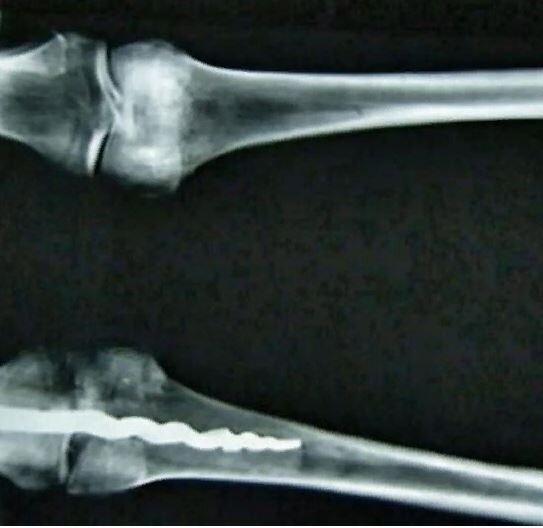

В 1971 году музей розенкрейцеров в Калифорнии приобрел запечатанный древнеегипетский гроб, содержащий хорошо сохранившуюся мумию высокопоставленного египетского мужчины. Более чем два десятилетия спустя группа ученых сделала шокирующее открытие – мумия продемонстрировала доказательства продвинутой хирургической процедуры, проведенной почти 2600 лет назад. Внутри левого колена мумии находился 9-дюймовый металлический ортопедический штифт, который был вставлен с такими передовыми биомеханическими принципами, что первоначально ученые не могли отличить его от современной операции.

В августе 1995 года профессор С. Уилфред Григгс из Университета Бригама Янга, штат Юта, и группа экспертов провели рентген шести мумий, размещенных в Музее Розенкрейцеров Сан-Хосе в преддверии лекции, которую он будет там читать, включая мумию Юзермонту. Они были ошеломлены, когда рентген показал, что у одной из мумий была 9-дюймовая металлическая булавка в левом колене.

Университет Бригама Янга (BYU) сообщает, что было невозможно увидеть, что металлический имплантат был древним только с помощью рентгеновского снимка, что привело профессора Григгса к мысли, что штифт был помещен туда в более современные времена, чтобы снова прикрепить ногу к остальной части тела.

Чтобы исследовать природу имплантата, Григгс, доктор Ричард Т. Джексон, хирург-ортопед из Прово, и доктор Э. Брюс Макифф, руководитель отдела радиологии регионального медицинского центра долины Юты, тщательно просверлили кость, чтобы крошечная камера могла исследовать штифт и извлечь образцы кости и металла.

Ученые обнаружили следы древней органической смолы, похожей на современный костный цемент, а также следы древних жиров и тканей, все еще прочно удерживаемых на месте. Обширные исследования показали, что эта усовершенствованная процедура была проведена в древние времена, приблизительно 2600 лет назад.

ByU сообщает, что штифт “сужается в штопор, когда он входит в бедренную кость, или бедренную кость, аналогично биомеханическим методам, используемым в настоящее время. Другой конец штифта, который расположен в большеберцовой или берцовой кости, имеет три фланца, выступающие наружу от сердцевины штифта, которые предотвращают вращение штифта внутри кости.”,